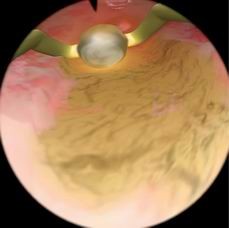

Essure植入体避孕模块

用于培训学员练习如何安置永久性节育装置